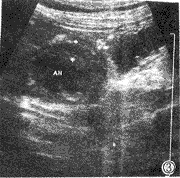

345例胃超声检查阳性患者108例,其结果显示如表1。浅表性胃炎、肥厚性胃炎典型表现如图2、图3所示。

图3 显示肥厚性胃炎,胃壁层次模糊、增厚(10mm)。